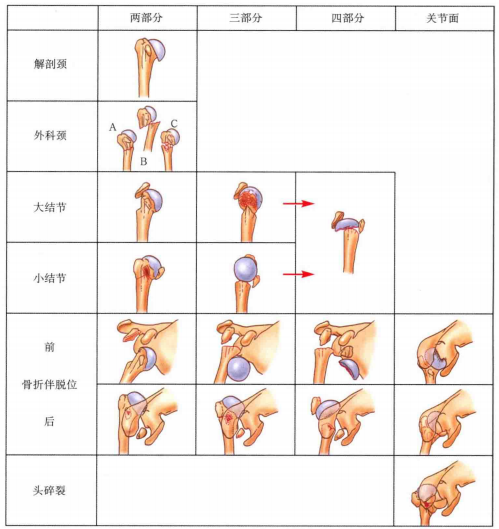

分型

第三部分是小结节和附着的肩胛下肌,具有内收和内旋的作用;

第四部分是肱骨干,从外科颈或结节下水平断裂。

11 C 型:关节内,四部分骨折(解剖颈)。